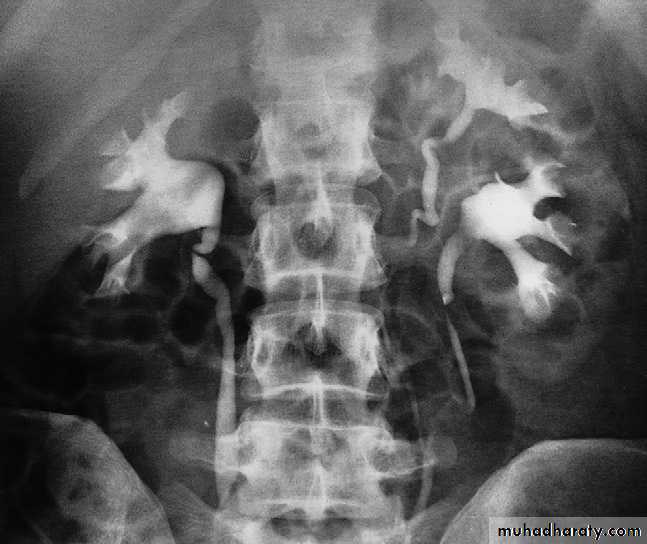

IVU study

-Plain film in intravenous urogram: it used to Identify all calcifications. Decide if they are in the kidneys by relating them to the renal outlines , calcification seen in the line of the ureters or bladder must be reviewed with post contrast scans, to determine whether the calcification lies in the renal tract. Note that calcification can be obscured by contrast medium and stones are missed if no plain film is taken.-Films taken after injection of contrast medium Kidneys

1 .Check that the kidneys are in their normal positions . The left kidney is usually higher than the right.2 .Identify the whole of both renal outlines. If any indentations or bulges are present they must be explained.

3 .Measure the renal lengths.Calices

The calices should be evenly distributed and reasonably symmetrical. The shape of a normal calix is ‘cupped’ and when it is dilated it is described as ‘clubbed .causes of dilated calcies

pelvis and ureters

The normal renal pelvis and pelvi-ureteric junction are funnel shaped. The ureters are usually seen in only part of their length on any one film of IVU because of obliteration of the lumen by peristalsis.Congenital variations of the renal collecting system are relatively common .